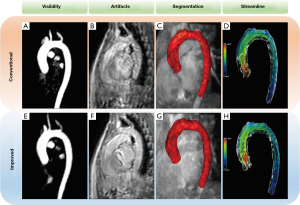

Visibility and artifacts: we implemented a tiered scoring system, ranging from 1 to 4 points. For visibility evaluation, end-diastolic PC angiography (PCA) images of the aorta within the 4D flow CMR scans were acquired with a window width/level of 198/181 (Figure 2C), and for artifacts evaluation, end-diastolic magnitude images were acquired with a window width/level of 1,440/829 (Figure 2D). The detailed scoring criteria is as follows (images were show in Figure S2).

Visibility: 1 point, low signal intensity with poor uniformity; 2 points, relatively higher signal intensity with sub-improved uniformity; 3 points, relatively higher signal intensity with good uniformity; 4 points, high signal intensity with excellent uniformity.

Artifacts: 1 point, severe artifacts with indistinct anatomical structures; 2 points, moderate artifacts with anatomical structures still discernible; 3 points, mild artifacts with better discernment of anatomical structures; 4 points, minimal artifacts with clear and discernible anatomical structures.

As shown in Table 3 and Table S1, a visibility score analysis revealed no statistically significant difference between the conventional and improved methods {3 [3–4] vs. 3 [3–4], P=0.15}. Among the participants, 10.91% (6/55) achieved higher scores with the improved method, whereas 3.64% (2/55) had better scores with the conventional method, with most [85.45% (47/55)] exhibiting equivalent scores across both methods.

When evaluating the presence of artifacts, the improved method had the advantage of reducing artifacts, with a median score of 2 (IQR, 2–3) compared to the conventional method’s median score of 2 (IQR, 1–2) (P<0.001). Specifically, 60% (33/55) of the participants had improved scores with the improved method, 5.45% (3/55) with the conventional method, and 34.55% (19/55) showed no difference in scores between the two methods. Figure 4 shows examples of the visibility, artifacts, and post-processing enhancement of the 4D flow CMR images obtained through conventional and improved diaphragmatic navigation.